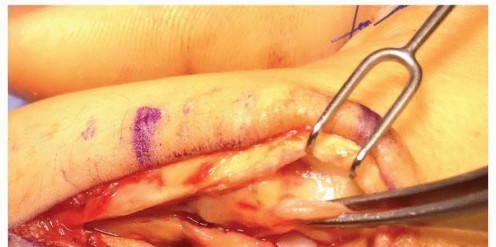

When closed reduction fails, or for complex, comminuted, or multiple metacarpal fractures, Open Reduction and Internal Fixation (ORIF) is mandated. A dorsal longitudinal or slightly gently curved incision is made centered over the fractured metacarpal. Careful subcutaneous dissection is performed to identify and meticulously retract the dorsal sensory nerve branches using vessel loops. The extensor apparatus is exposed. Depending on the fracture location, the extensor tendon can be retracted laterally, or the extensor mechanism can be split longitudinally (e.g., splitting the EDC tendon) to access the dorsal periosteum.

Periosteal elevation must be judicious and strictly limited to the footprint required for plate application. Circumferential stripping of the periosteum is a catastrophic error that devascularizes the bone fragments and invites nonunion. The fracture site is gently debrided of hematoma and interposed soft tissue. Anatomical reduction is achieved using specialized reduction forceps, taking immense care to avoid crushing fragile cortical edges. Provisional fixation is maintained with fine (0.035-inch or 0.045-inch) K-wires.

Clinical & Radiographic Imaging Archive